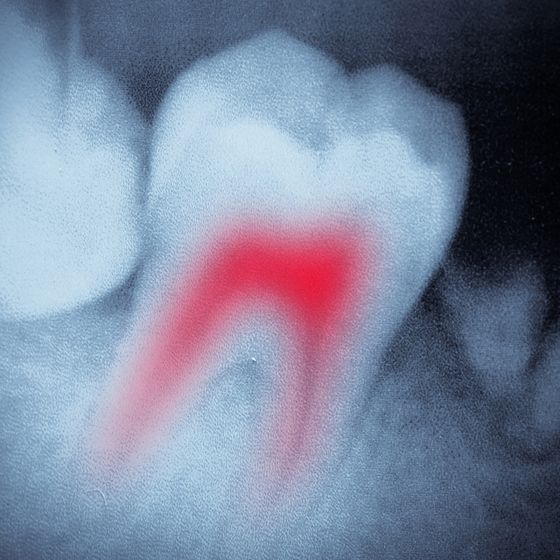

Root Canal Therapy

If you have an infected or badly damaged tooth, root canal therapy may be the most appropriate treatment. This procedure can save a natural tooth that would otherwise need to be removed. After numbing your tooth and surrounding area, Dr. Slaman will clean out the inside chamber and your root canals. Once he has filled your tooth with a rubber-like material, he will seal it and place a custom-made dental crown. With our innovative CEREC® system, Dr. Slaman can provide qualified patients with same-day root canal therapy.